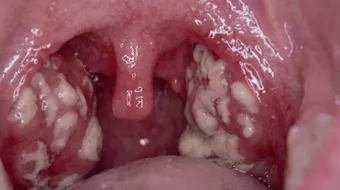

تُعرف اللوزتين بأنّهما زوج من الأنسجة الرخوة الموجودة في مؤخرة الحلق أو ما يُسمى بالبلعوم (بالإنجليزية: Pharynx)، وتتكون اللوزتين من أنسجة مشابهة للغدد الليمفاوية، وتكون مغطاة بغشاء مخاطي وردي، وقد تتفاوت في الحجم من شخص إلى آخر، وتُعدّ الوزتين جزءاً مهماً من الجهاز الليمفاوي الذي يساعد على محاربة العدوى؛ إذ تتضخم اللوزتين استجابة للعدوى، وعلى الرغم من ذلك فقد وُجد أنّ إزالة اللوزتين لا تزيد من فرصة الإصابة بالعدوى.[1]

هناك مجموعة من الأسباب التي تؤدي إلى وجود بقع بيضاء على اللوز أو ما يُعرف بصديد اللوز، ويعتمد علاج صديد اللوز على المسبب الذي أدَّى إلى ظهوره،[2] وفيما يلي بيان لأهم أسباب صديد اللوز وعلاج كل منها:

قد تظهر على المصاب بعض الأعراض تدل على احتمالية تشكل صديد اللوز، ومن هذه الاعراض ما يلي:[9]

- انتفاخ أو التهاب أجزاء من الفم والحلق وعادة ما يكون ذلك في جانب واحد.

يُعرف التهاب اللوز (بالإنجليزية: Tonsillitis) بأنّه عدوى تصيب اللوزتين، وغالباً ما يحدث نتيجة التعرض لعدوى فيروسية، كما يمكن أن ينجم التهاب اللوزتين عن التعرض لبعض أنواع البكتيريا،[10] ومن الجدير بالذكر أنّ المضاعفات التي يُمكن أن تنجم عن التهاب اللوزتين تُعتبر نادرة الحدوث، وتتضمن هذه المضاعفات ما يأتي:[11]